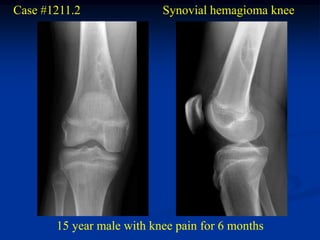

Case #1211.2               Synovial hemagioma knee

15 year male with knee pain for 6 months

Coronal T-1   Coronal T-2

Axial T-2

Surgical exposure at time of excisional biopsy

Case #1211.2 Synovial hemagioma knee 15 year male with knee pain for 6 months

• 363.

• 364.

• 365.

Surgical exposure attime of excisional biopsy